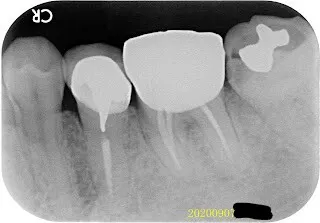

假牙材質11-根尖病變+除汞+智齒

我忘了這位病人後來是否有來做後續的治療,我猜應該是沒有,因為我沒印象。但我那時都已經幫他精心劃好治療計畫的圖(方便他理解龐大的工程,對,這就像預售屋之類的藍圖)。 就不浪費了,剛拿來紙上談兵,模擬計畫,what if一下。